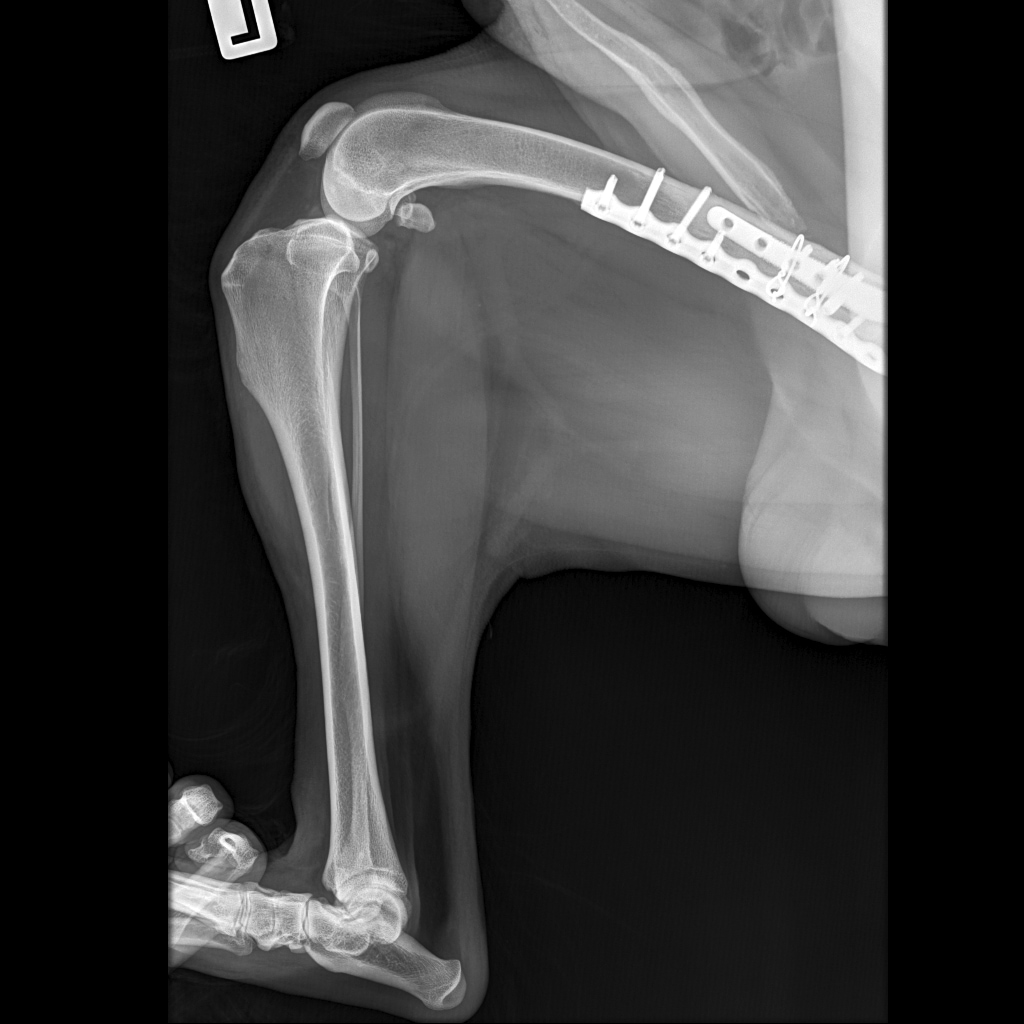

Вчера резко захромал, встал на 3 ноги и понос.

По рентгену чисто

В понедельник КТ